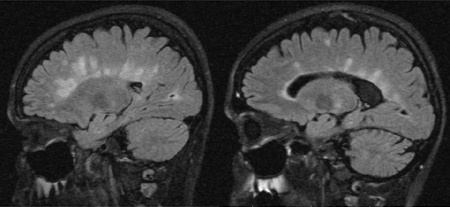

Imagens FLAIR (recuperação de inversão atenuada por fluido) sagitais podem ajudar a distinguir entre lesões de EM e alterações inespecíficas da substância branca, como as observadas em associação com hipertensão, diabetes, idade >50, tabagismo, enxaqueca, colesterol alto e exposição a toxinas.[Figure caption and citation for the preceding image starts]: Imagens sagitais em recuperação de inversão atenuada por fluido (FLAIR) com lesões de esclerose múltipla (EM) típicas envolvem o corpo caloso, seja como lesões distintas ou como projeções semelhantes a dedos perpendiculares ao corpo caloso. Observe também o aumento dos ventrículos e a atrofia difusa da EM mais avançadaDo acervo do Dr. Lael A. Stone [Citation ends].